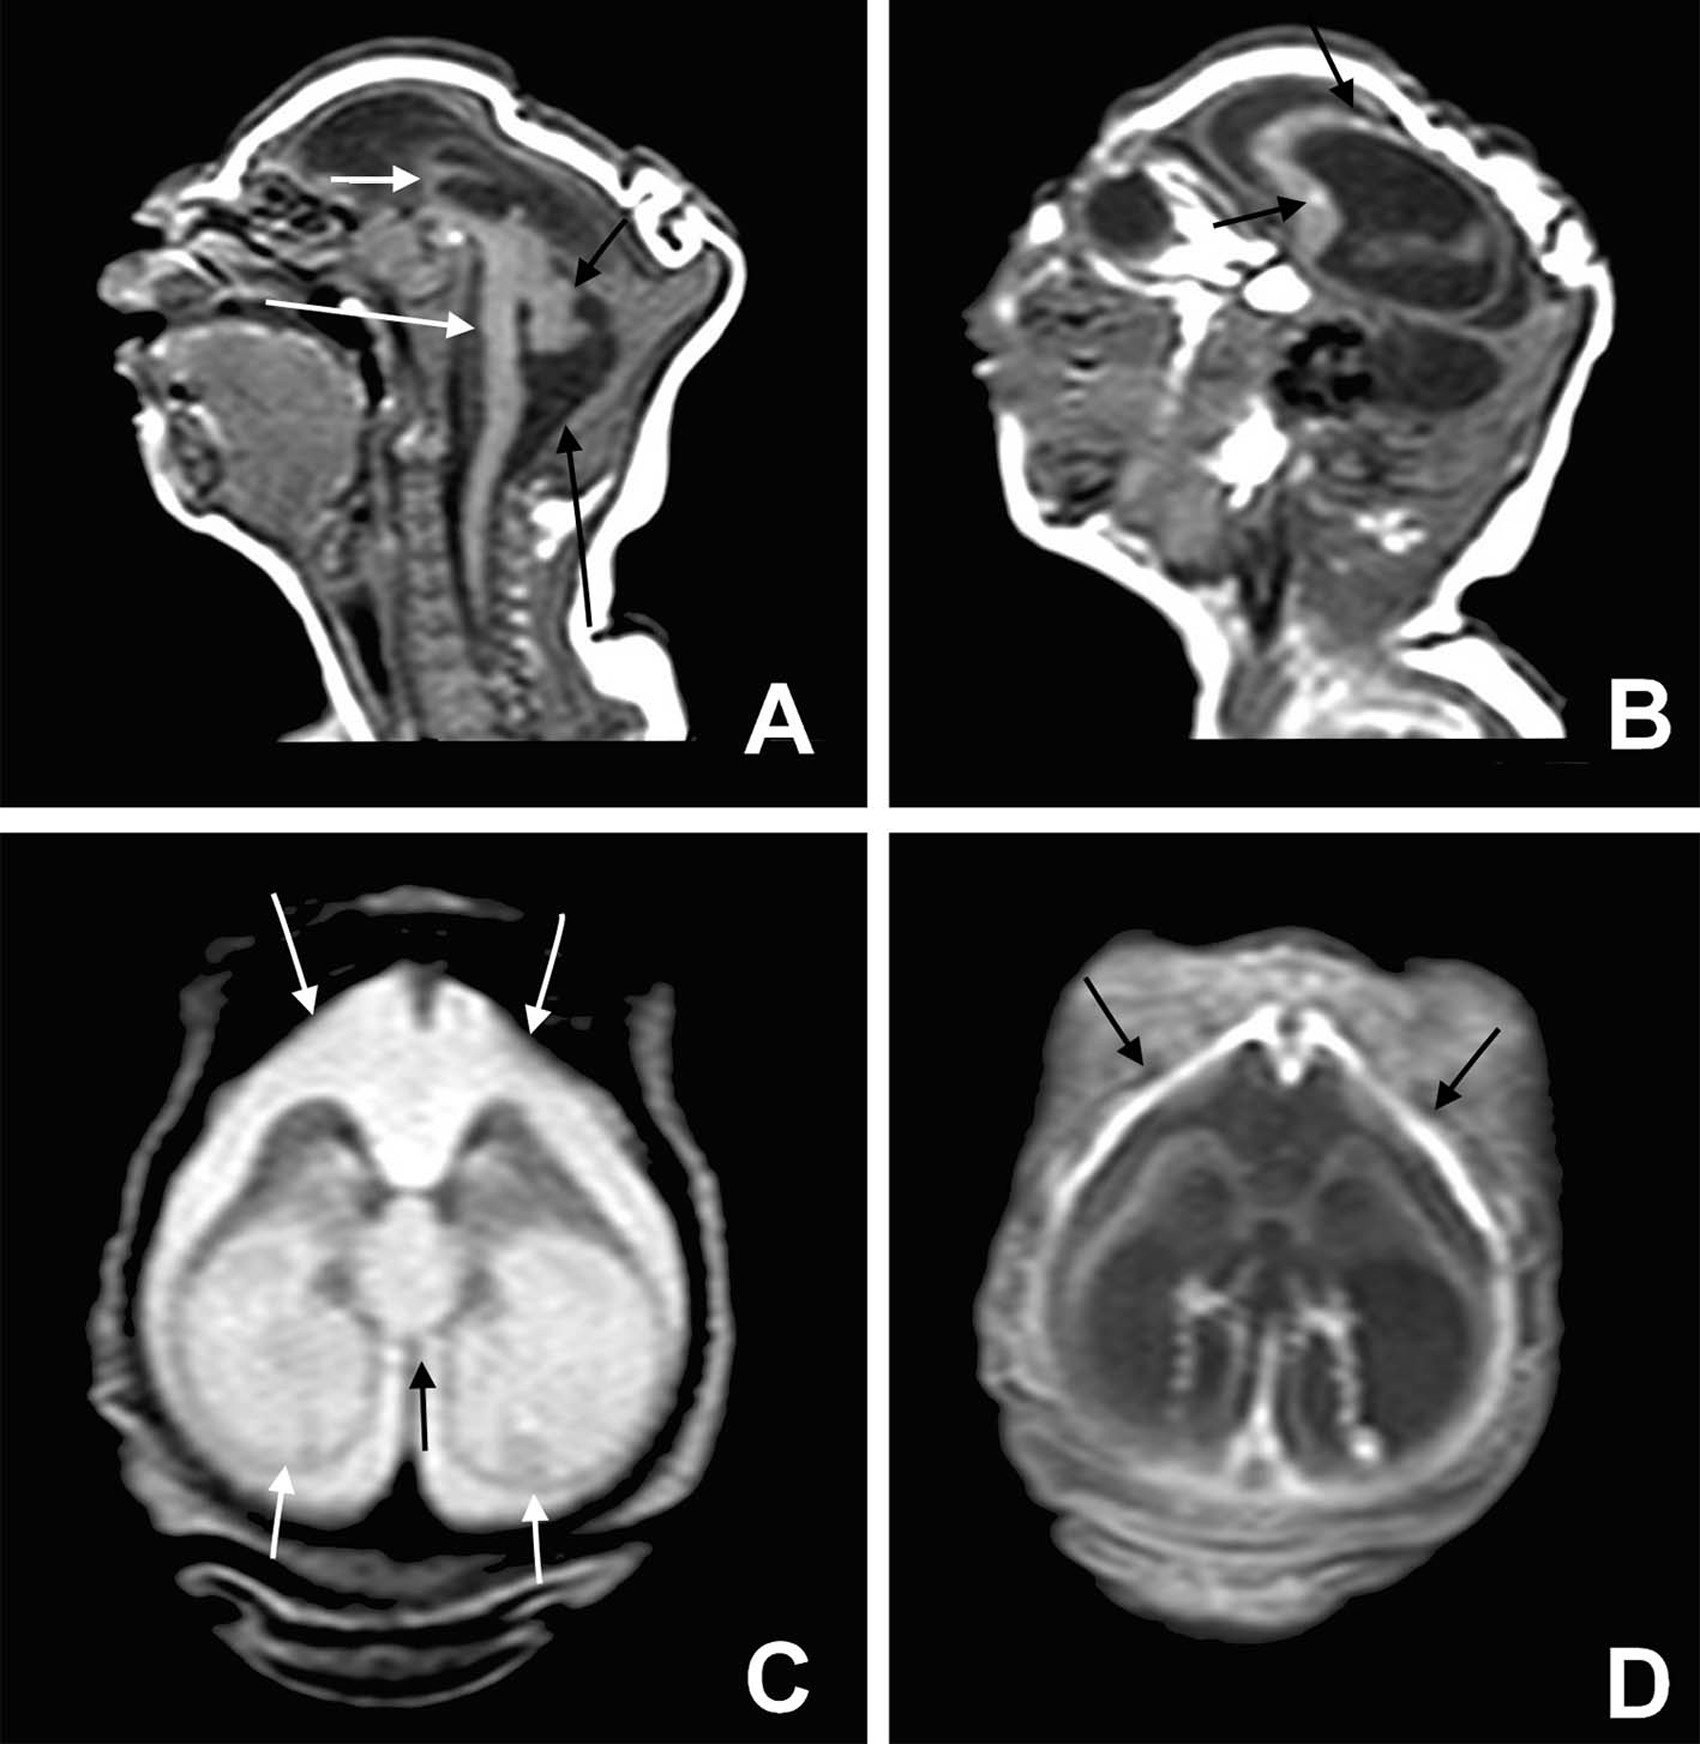

Exame de imagem revela danos cerebrais de bebês com microcefalia (Foto: BMJ 2015/ http://www.bmj.com/cgi/doi/10.1136/bmj.i1901 )

Um estudo brasileiro publicado na revista "British Medical Journal" nesta quarta-feira (13) detalhou os tipos de problemas presentes no cérebro de bebês com microcefalia relacionada à zika. Este é o primeiro estudo que faz uma tentativa de distinguir as características cerebrais de bebês com microcefalia ligada à zika daquelas observadas em bebês com microcefalia devido a outras infecções.

A pesquisa concluiu que a microcefalia ligada à zika apresenta, em geral, danos cerebrais extremamente severos, com poucas chances de um bom desenvolvimento das funções neurológicas. Uma característica que parece ser específica da microcefalia por zika é a calcificação em uma região determinada: entre a substância branca cortical e subcortical do cérebro.

A hipótese dos autores é que o vírus da zika destrói células cerebrais e forma lesões parecidas com cicatrizes, onde há depósito de cálcio.

As crianças nasceram em Pernambuco entre julho e dezembro de 2015. Desse grupo, 15 passaram por tomografia computadorizada, 7 passaram tanto por tomografia quanto por ressonância magnética e um passou apenas pela ressonância.